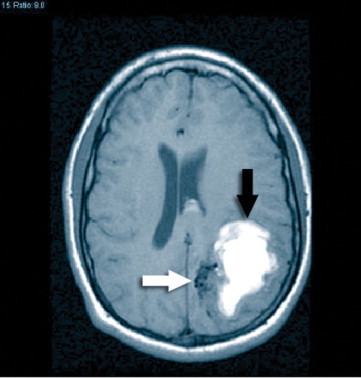

61 y/o man with history of poorly controlled HTN did not show up for work. His son found him on the floor, confused, speaking with slurred speech and unable to get up.

Exam showed dysarthria, moderate right sided weakness, and right sided sensory loss

• Vitals: 230/135, HR 104, RR 27

whats the etiology?

Hyaline aretherosclerosis

Infarct in the parietal cortex is likely to be due from:

an embolism